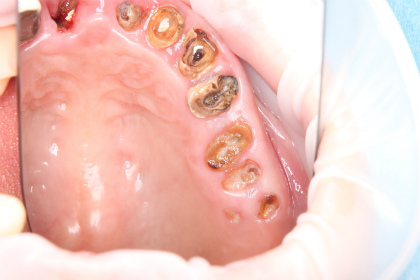

所谓残根,是指牙冠被破坏以后所剩余的牙根。由于失去正常的咬合,故在日常的咀嚼活动中不能发挥作用。

残根

需要拔除的残根